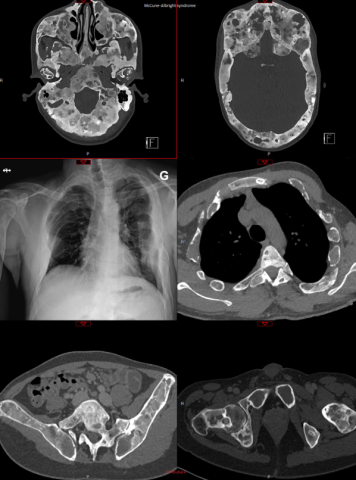

ECR2026 fig2.png

McCune–Albright syndrome